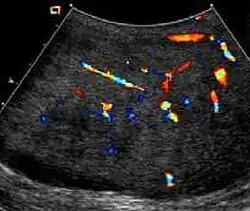

At ultrasound, the findings of acute epididymitis include an enlarged hypoechoic or hyperechoic (presumably secondary to hemorrhage) epididymis [Fig. 20a]. Other signs of inflammation such as increased vascularity, reactive hydrocele, pyocele and scrotal wall thickening may also be present. Testicular involvement is confirmed by the presence of testicular enlargement and an inhomogeneous echotexture. Hypervascularity on color Doppler images [Fig. 20b] is a well-established diagnostic criterion and may be the only imaging finding of epididymo-orchitis in some men.

Doppler ultrasound of epididymitis, seen as a substantial increase in blood flow in the left epididymis (top image), while it is normal in the right (bottom image). The thickness of the epididymis (between yellow crosses) is only slightly increased (7 mm). -

Doppler ultrasound of the scrotum of the same case, in the axial plane, showing orchitis (as part of epididymo-orchitis) as hypoechogenic and slightly heterogenic left testicular tissue (right in image), with an increased blood flow. There is also swelling of peritesticular tissue.